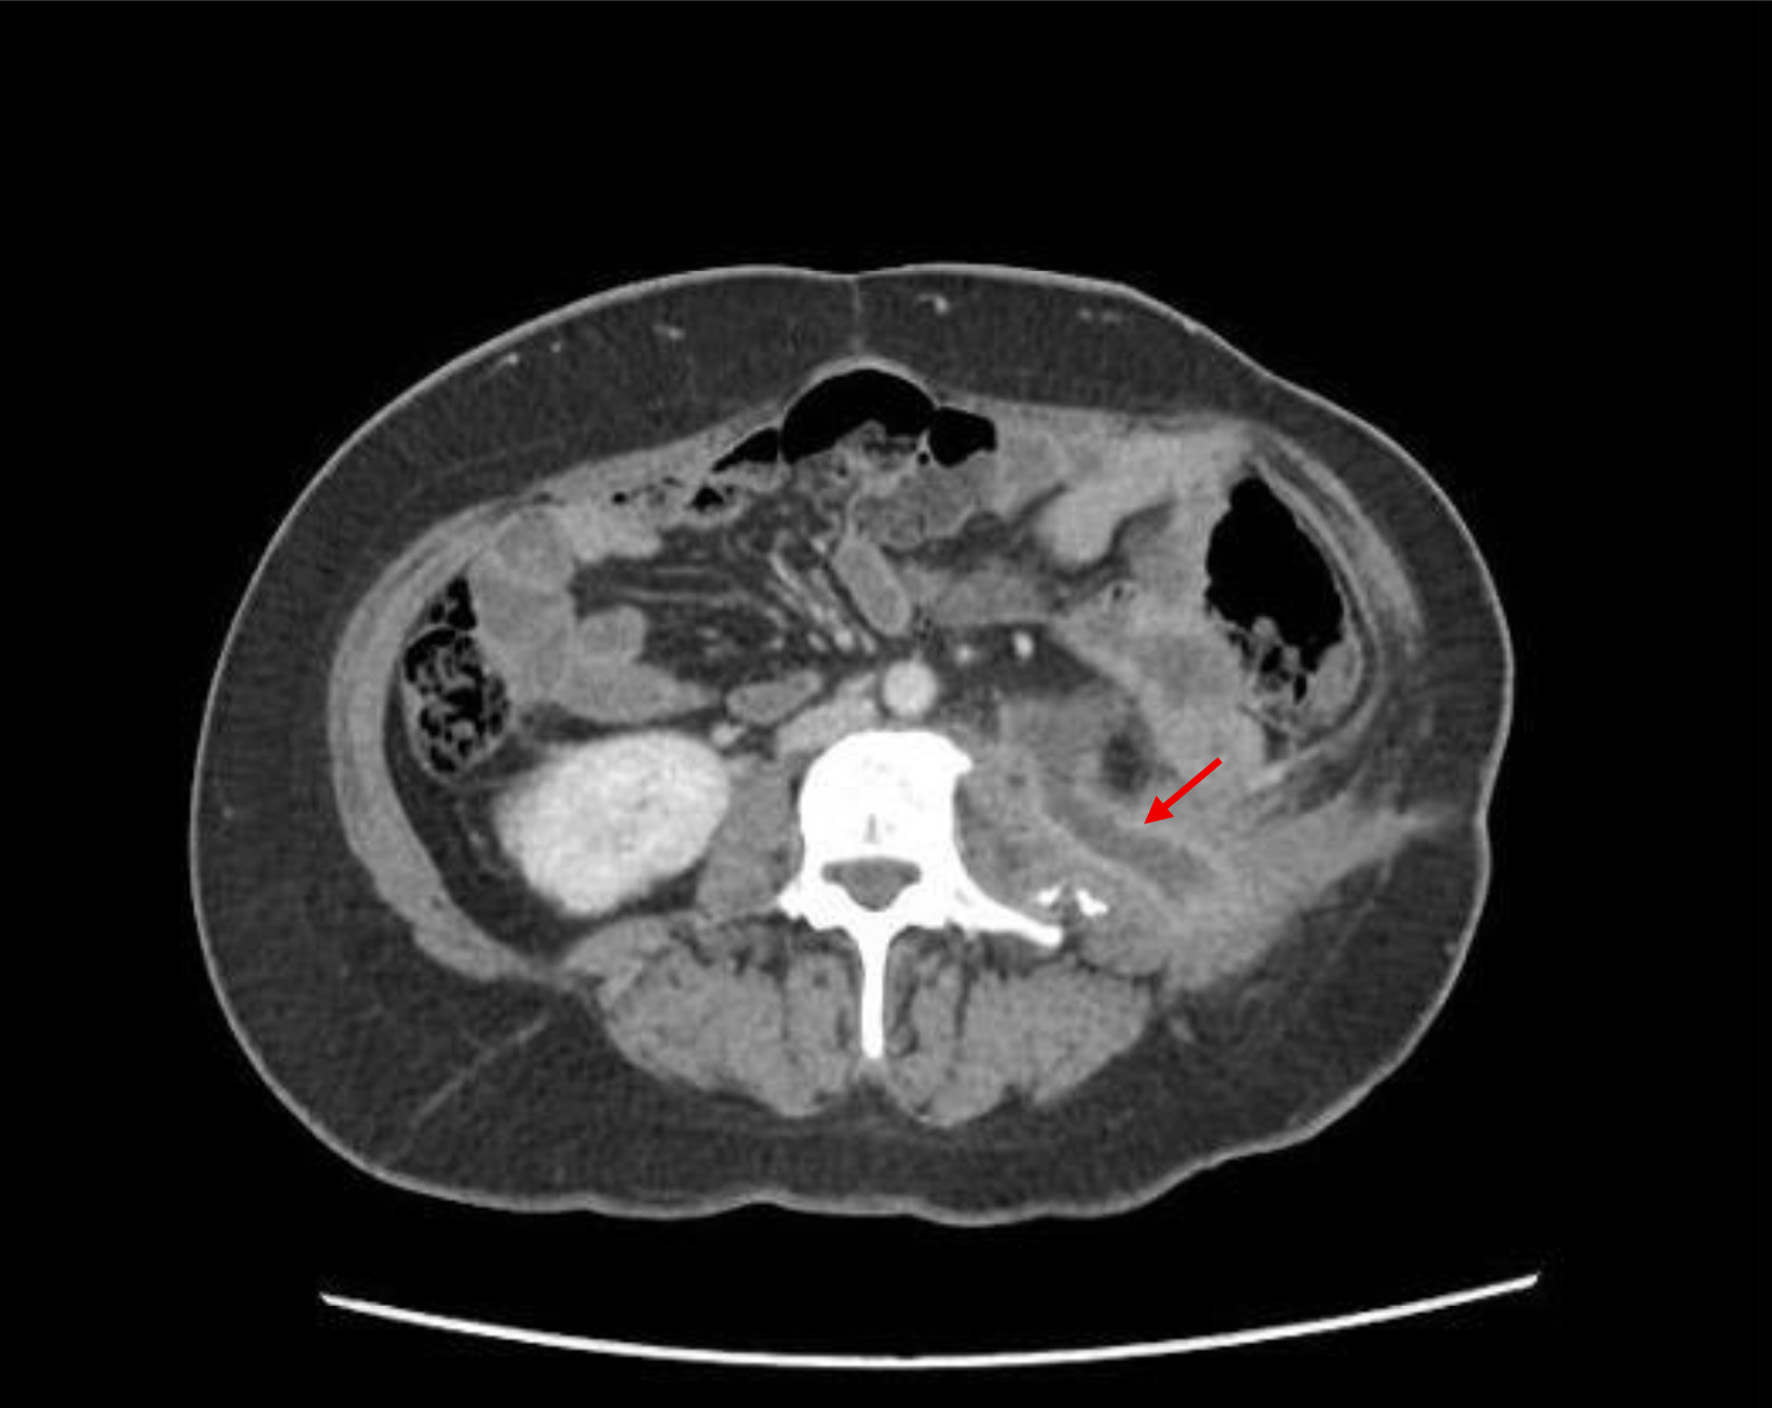

A contrast-enhanced computed tomography (CT) scan (Fig. 2) was ordered, which revealed a large cutaneous fistula in the lumbar region extending to the urinary bladder, with potential involvement of the left distal ureter, although no contrast reflux was observed within the fistula tract. The fistula tract measured approximately 28 mm to the skin surface.

Figure 2. Transverse plane of contrast-enhanced computed tomography (CT) scan showing a cutaneous tract on the left side measuring approximately 28 mm in length (arrow), along with evidence of prior left nephrectomy.